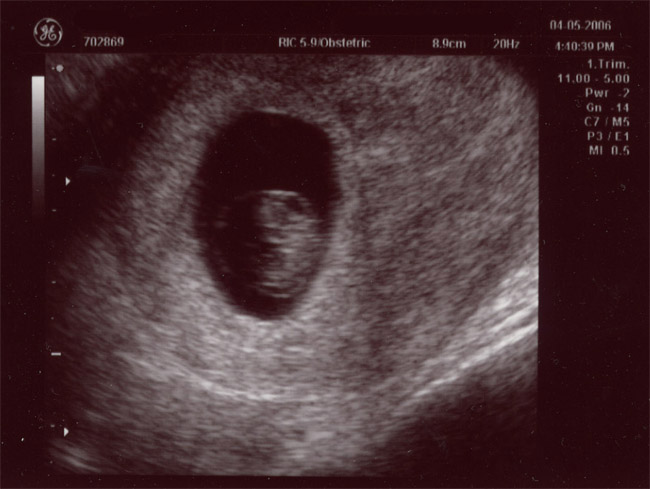

| April 5, 2006 - Eight Week Ultrasound (The First Pics of Baby Palermo!) |

| I was having some

spotting this morning and I was pretty worried. I immediately called

the doctor and they told me to come in around 1:30pm. It was pretty

tough to stay at work for a couple of hours before my appointment since I

really wasn't sure what was going on. When I got to the doctor's

office, they saw me right away and the doctor didn't seem too worried.

She did want to do an ultrasound just to be sure that little baby was

staying as cozy as possible in there. They did the ultrasound and

everything was just fine. The baby was measuring 4 days ahead of

schedule and I was so excited to see the baby moving all over the place.

Today, I got my official due date--November 15, 2006. YAY!!! ~Jen |